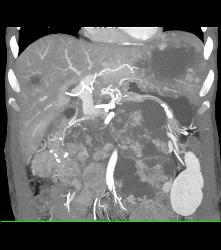

Patent Stents in Renal Arteries